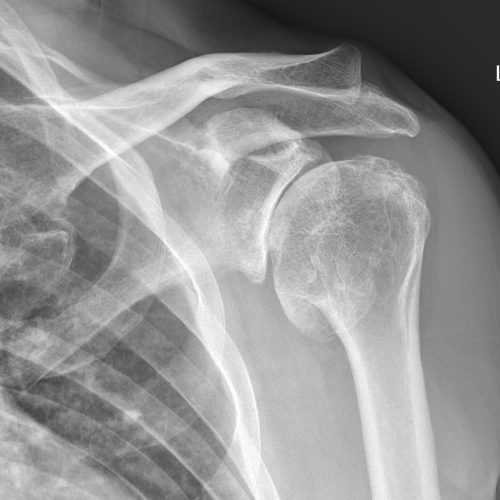

Normal anatomy: The shape of the acromion bone differs from person to person and may be flat, curved, or hooked, which may predispose the shoulder to impingement.

Imaging: X-rays can rule out other causes like bone spurs, while ultrasound or MRI can visualize inflamed bursae or associated tendon problems.